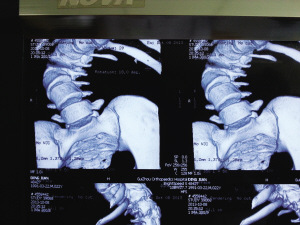

今年1月,小健感覺身體不適,便在親友陪同下來到省骨科醫院。經檢查,醫生發現小健脊柱后凸彎近150度,側凸近130度,肺功能受損達30%。因小健已經22歲,脊柱生長已經停止,十分僵硬,錯過了最佳治療期,只能做脊柱側彎矯正手術,但該手術費用高,難度大。

8個小時的手術中,小健共被植入19根金屬釘。手術成功后,小健背部包塊不見了,身高從156公分“躥”到168公分。昨日,出院后的小健來到醫院復查,恢復結果良好。